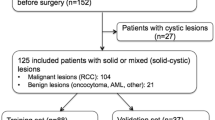

Solid renal masses (SRM) are difficult to differentiate based on standard MR features. The purpose of this study was to assess MR imaging features of SRM to evaluate performance of ensemble methods of classifying SRM subtypes.

MR images of SRM (n = 330) were retrospectively evaluated for standard and multiparametric (mp) features. Models of MR features for predicting malignant and benign lesions as well as subtyping SRM were developed using a training dataset and performance was evaluated in a test data-set using recursive partitioning (RP), gradient booting machine (GBM), and random forest (RF) methods.

In the test dataset, GBM and RF models demonstrated an accuracy of 86% (95% CI 75% to 93%) for predicting benign versus malignant SRM compared to 83% (95% CI 71% to 91%) for the RP model. RF had the greatest accuracy in predicting SRM subtypes, 81.2% (95% CI 69.5% to 89.9%) compared with GBM 73.4% (95% CI 60.9% to 83.7%) or RP 70.3% (95% CI 57.6% to 81.1%). Marginal homogeneity was reduced by the RF model compared with the RP model (P < 0.001), but not the GBM model (P = 0.135). All models had high sensitivity and specificity for clear cell and papillary renal cell carcinomas (RCC), but performed less well in differentiating chromophobe RCC, oncocytomas, and fat-poor angiomyolipomas.

Ensemble methods for prediction of SRM from radiologist-assessed image characteristics have high accuracy for distinguishing benign and malignant lesions. SRM subtype classification is limited by the ability to categorize chromophobe RCCs, oncocytomas, and fat-poor angiomyolipomas.